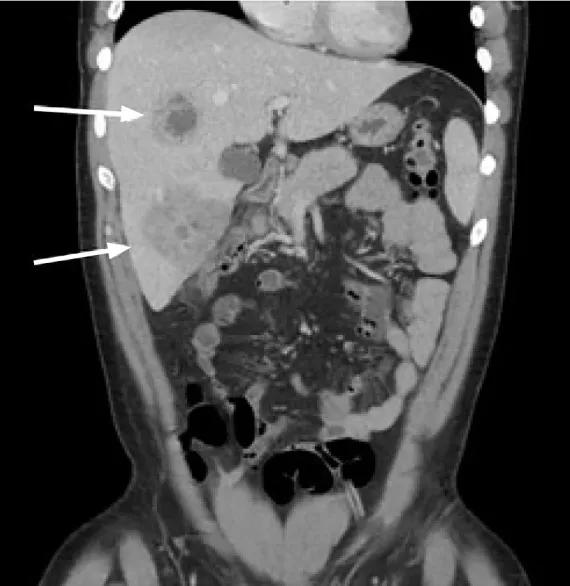

首先映入眼帘的是肝脏多发脓肿(图1)!

图1.多发肝脓肿形成